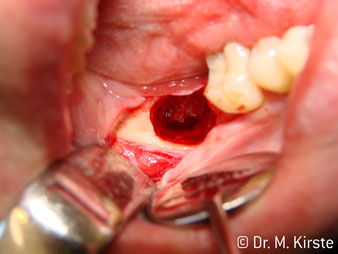

La concezione professionale del sistema di cuscinetti nel cuore della testina del contrangolo assicura un funzionamento silenzioso delle frese; durante l'estrazione di denti e radici (Fig. 4 - 9) si ottiene un taglio estremamente preciso e stabile.

Fig. 4